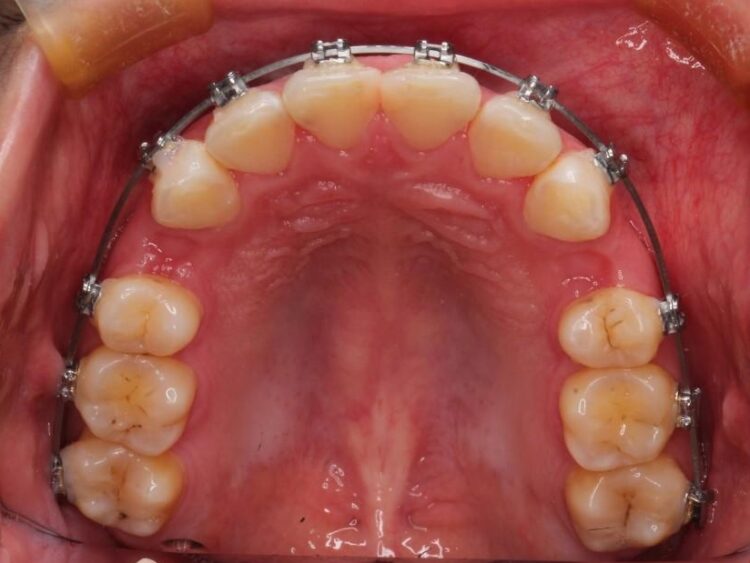

- 矯正装置:メタル装置

治療費の安い矯正治療を希望されていたため、メタルのワイヤー装置にて治療する計画にしました。また、歯みがきが苦手だったため、矯正治療をする前に徹底的にブラッシング指導を行いました。

出ている歯を引っ込めるためのスペースを作るため、上下左右の小臼歯を抜歯し、ワイヤー矯正を行いました。治療後は、口元がスッキリとしたことで患者様にも喜んでいいただきました。